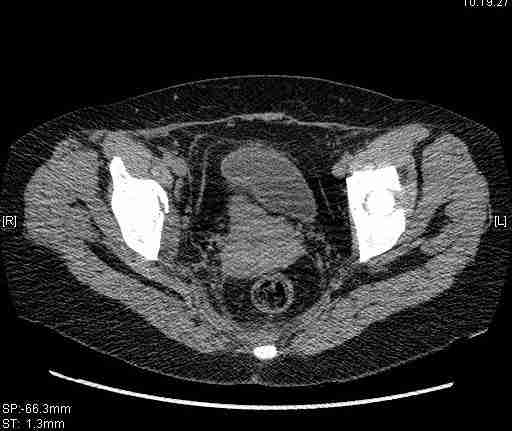

Удалось сегодня вывести пациентку в соседнюю больницу, где есть кт. Срезы сделаны только горизонтальные.

Следом 3d